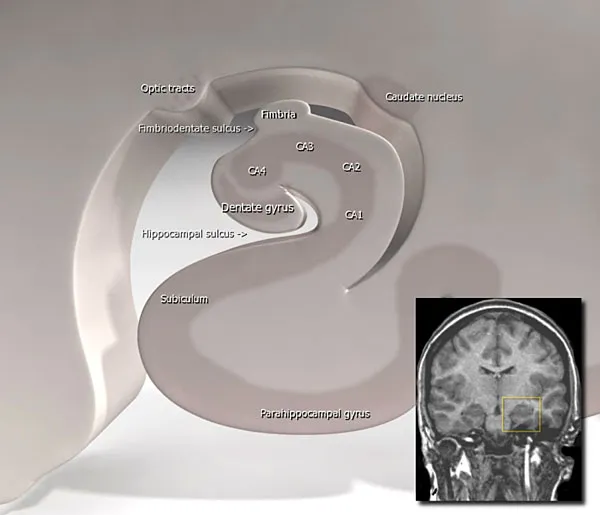

Section titled “The Seahorse in the Brain”There is a seahorse in the brain, called the hippocampus, from the Greek for “seahorse”. The illustration below shows the seahorse shape, while the red rectangle in the CT image shows the location of the hippocampus. (In the large image, the brain is shown in grey, superimposed over a whitish background with a shadow. The "seahorse" faces left.)

Figure 1: The Hippocampus

The beautiful hippocampus promotes memory and spatial orientation. Since Alzheimer's especially affects the hippocampus, memory and navigation are the first faculties people with Alzheimer's lose.